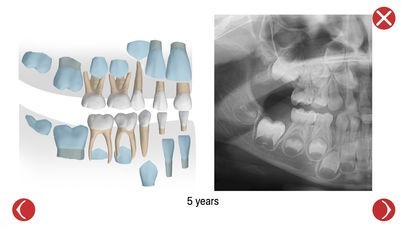

Dental Corpus PRIMARY is an interactive application for dental students, dentists, health professional, assistants and pediatric patients. The application is very functional for understanding and visualizing the complexity of root anatomy of the primary (deciduous) teeth. It can also help the user learn detailed information about the size, the morphology and the development of each tooth, emphasized on the differences between primary and permanent teeth. 3D tooth models were created according to various studies about primary teeth morphology, gathered from the latest dental papers and references. A combination of X-rays and illustrations during primary teeth development, supported by a plethora of references make this app a unique tool for any educational purpose. There is also the possibility to obtain all this information in printable pdf version.